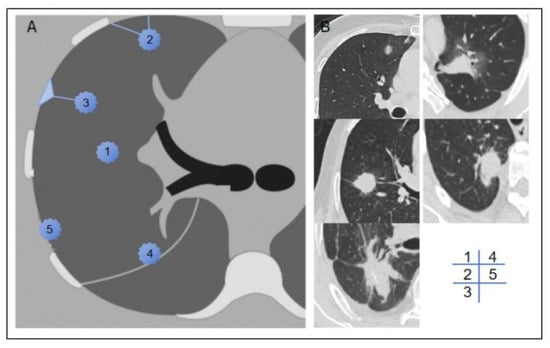

We documented the demographic information, laboratory test results, and tumor marker levels of all enrolled patients. These data included variables such as sex, age, BMI, smoking history, neutrophil-to-lymphocyte ratio (NLR), platelet-to-lymphocyte ratio (PLR), lymphocyte-to-monocyte ratio (LMR), prothrombin time (PT), activated partial thromboplastin time (APTT), fibrinogen (FIB), D-dimer levels, and a panel of tumor markers, including carcinoembryonic antigen (CEA), carbohydrate antigen 125 (CA125), carbohydrate antigen 19-9 (CA19-9), human CYFRA21-1 antigen (CYFRA21-1), and neuron-specific enolase (NSE). Preoperative CT scans were utilized to assess the patients’ clinical T stage (cT stage) and to evaluate the relationship between the tumor and pleura. Based on previous studies [12], we classified the tumor–pleura relationship into five distinct types, ranging from tumors confined to the lung parenchyma to those in direct contact with the parietal pleura (as illustrated in Figure 2).

Figure 2. Schematic diagram (A) and representative imaging examples (B) of type 1–5 tumor–pleura relationships. In type 1, tumor is located inside lung and is unrelated to pleura. In type 2, tumor is not in contact with pleura, and one or more linear or striated pleural tags are visible. In type 3, tumor is not in contact with pleura, and one or more linear or striated pleural tags with soft tissue components at pleural end are visible. In type 4, tumor is in contact with interlobar pleura. In type 5, tumor is in contact with parietal pleura.